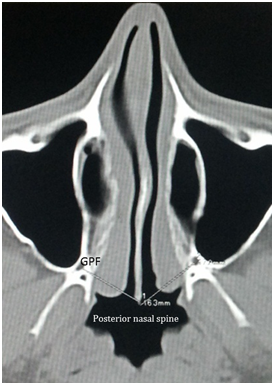

Measurements of the distance between the GPF and the incisive foramen (IF), the posterior nasal spine (PNS), the intermaxillary suture (IMS), as well as the second (M2) and third (M3) molars was done. In the axial plane, after identification of GPF, distance between the incisulare was measured. The centre of the GPF was established while measuring its anterior-posterior (AP) and transverse dimensions. The centre of the GPF was set at the point of the intersection of two straight lines representing the longest AP and transverse GPF dimensions. Location and distance of GPF from lateral border of molars noted next at higher axial slice. Distances from intermaxillary suture and from PNS were noted at still higher planes having GPF point fixed. The data was tabulated and analysed using MS-excel software. Comparisons were by student t test and values <0.05 was considered significant.

From the department of Radiology, forty-four CT scans were included for the study. Out of which 30 were males and 14 were females. Mean age was 32 (±2.3)years. All scans were from individuals of south Indian origin. GPF was located at 38.38mm from incisive fossa, 17.6mm from posterior nasal spine (PNS), 18.38mm from intermaxillary suture, 5.03mm from second molar and 5.28mm from third molar. Measurements on right and left sides are tabulated in Table 1. Distances of GPF from incisive foramen and intermaxillary suture differed significantly on right and left sides. No such significant changes noted in distances from molars. In 25 (56.8%) cases GPF was located closer to third molar. In seven cases, it was closer to second molar and in 12 cases, GPF was located at the junction of second and third molar. Posterior location of GPF, posterior to third molar is not noted (Figure 1).

Figure 1 Measurement of distance from greater palatine foramen (GPF) to posterior nasal spine (blue arrow); point of greater palatine foramen is fixed and at a lower slice of CT scan other distances are measured.